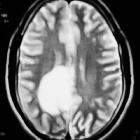

- T1 C+ (Gd)

- about half of tumefactive demyelinating lesions demonstrate contrast enhancement

- the enhancement pattern is usually in the form on an open ring and the incomplete portion of the ring is on the grey matter side of the lesion